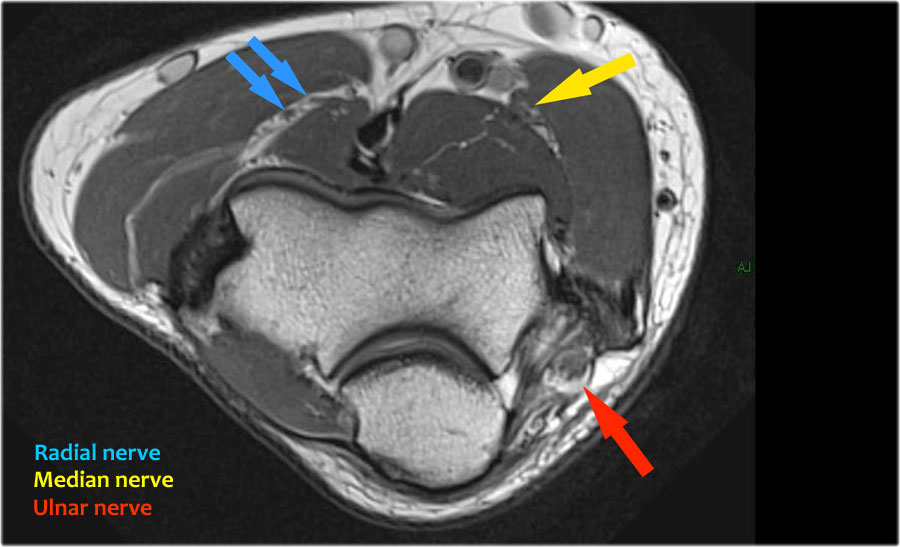

Radial nerve

Dây thần kinh quay có thể được xác định rõ nhất ở mức chỏm xương quay, nơi có thể quan sát thấy các nhánh nông và nhánh sâu trong ống xương quay (mũi tên).

This is a very consistent place to find the radial nerve.

Các nhánh quay sâu tạo thành thần kinh gian cốt sau xuyên qua cơ ngửa tại cung Frohse (mũi tên).